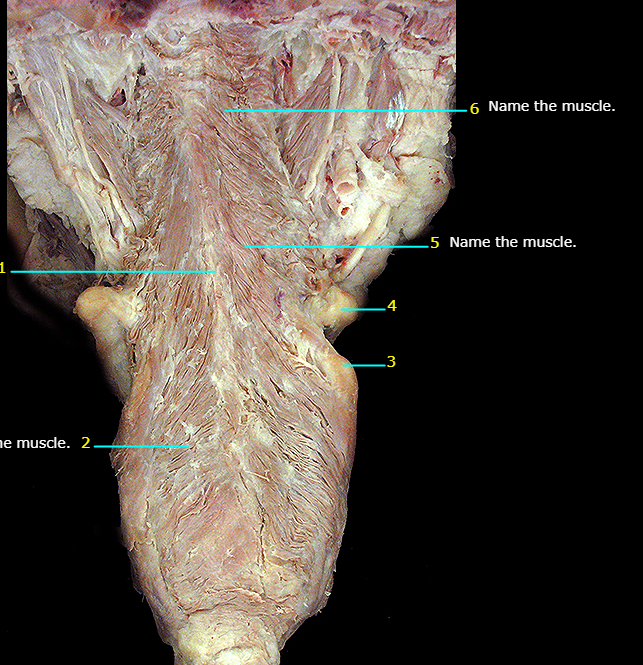

Name the muscle

Genioglossus m.

Hypoglossus m.

Styloglossus m.

Posterior cricoarytenoid m.

Anterior scalene m.

Middle scalene m.

Posterior scalene m.

Longus capitis m.

Longus colli m.